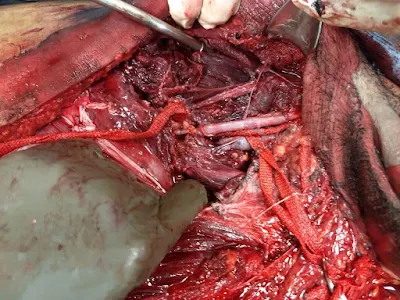

PACIENTE ADOLESCENTE DE 15 AÑOS DE EDAD DEL SEXO MASCULINO, EL CUAL INGRESA AL ÁREA DE URGENCIAS POSTERIOR A SER ATROPELLADO POR CAMIÓN, SE DETECTA TRAUMATISMO SEVERO PÉLVICO, CHOQUE HEMORRÁGICO INTERNO IV GRADO, HEMATOMA PULSÁTIL EN INGLE IZQUIERDA CON INSUFICIENCIA ARTERIAL DE LA EXTREMIDAD, SE TOMA TOMOGRAFIA SIMPLE POR LOS MEDICOS DE URGENCIAS SIN MEDIO DE CONTRASTE CON HALLAZGOS DE FRACTURA PÉLVICA, EL PACIENTE SE SOMETIÓ DE MANERA URGENTE A LAPAROTOMIA Y SE ENCONTRÓ A NIVEL VASCULAR DESGARRO Y PÉRDIDA DE LA CONTINUIDAD DE ILIACA COMÚN A SU PASO A ILIACA EXTERNA CON SANGRADO Y HEMATOMA EXPANSIVO, TROMBOSIS DISTAL DE ILIACA, EL JOVEN SE SOMETIÓ A COLOCACIÓN DE INJERTO DE SAFENA INVERSA DE ILIACA IZQUIERDA Y PREVIA TROMBÉCTOMIA DISTAL DE VASOS FEMORALES, POPLITEOS Y TIBIALES RECUPERANDO FLUJOS DISTALES DE LA EXTREMIDAD PELVICA IZQUIERDA, POSTERIORMENTE PASÓ A TERAPIA INTENSIVA EN GRAVEDAD EXTREMA, ESPERANDO SER ESTABILIZADO DE SUS FRACTURAS POR ORTOPEDIA.

IDENTIFICACIÓN DE LA LESIÓN DE ILIACA

INJERTO SAFENA INVERSA COLOCADO ARTERIA ILIACA IZQUERDA

VIDEOS DEL INJERTO DE SAFENA FUNCIONAL

LAS LESIONES DE VASOS ILIACOS SON LAS MÁS SEVERAS EN TRAUMATISMOS PELVICOS CON UNA MORBIMORTALIDAD MAYOR DEL 90% DE LOS PACIENTES YA QUE SON CAUSANTES DE SANGRADOS MASIVOS HEMORRAGICOS CON FALLA RENAL Y SISTÉMICA A ORGANOS SINO SE RESTITUYE EL VOLUMEN SANGUÍNEO DE MANERA ADECUADA, ES INDISPENSABLE QUE LOS CENTROS DE URGENCIAS IDENTIFIQUEN Y SEPAN MANEJAR DE FORMA ADECUADA A ESTOS PACIENTES DESDE QUE INGRESAN A SUS SALAS, ASI COMO LA ESTABILIZACIÓN DE ESTAS FRACTURAS EN EL MISMO TIEMPO QUIRÚRGICO.